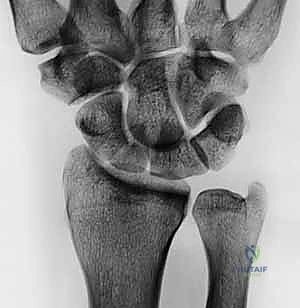

الأشعة السينية المتخصصة (X-rays)

لا تُكتفى بصورة أشعة عادية، بل يتم طلب "مناظر العظم الزورقي الخاصة" (Scaphoid Views) بوضعيات محددة لليد (مثل الانحراف الزندي - Ulnar Deviation) لإبراز العظم الزورقي بوضوح. تُظهر الأشعة السينية وجود الفجوة، التصلب العظمي (Sclerosis)، أو التكيسات التي تدل على عدم الالتحام.

التصوير المقطعي المحوسب (CT Scan)

يُعد التصوير المقطعي المعيار الذهبي (Gold Standard) لتأكيد عدم التحام العظم الزورقي وتقييم التشوه الهندسي للعظم. يوفر الـ CT Scan صوراً ثلاثية الأبعاد دقيقة للغاية توضح حجم الفجوة العظمية، درجة زاوية التشوه (Humpback Deformity)، ومقدار العظم المفقود، مما يساعد الدكتور هطيف في التخطيط الدقيق لحجم الطعم العظمي المطلوب.